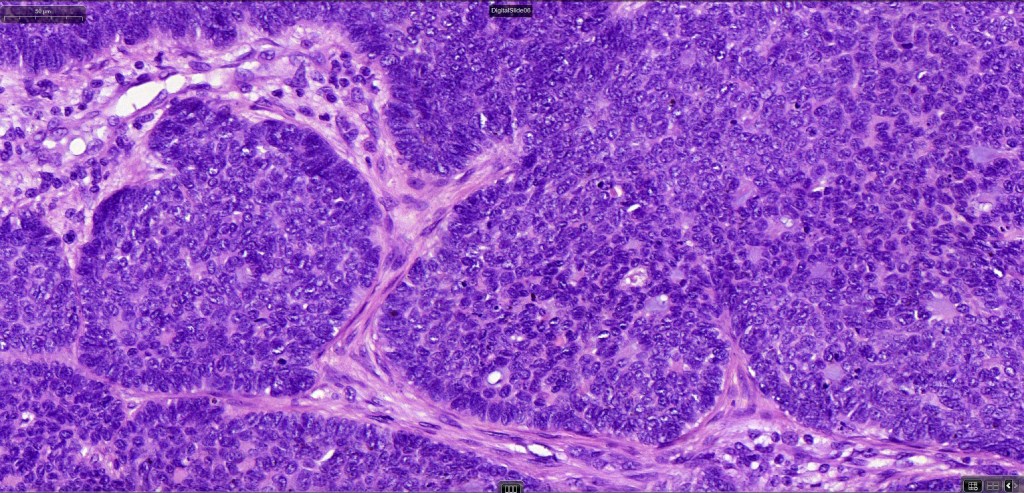

•The epithelial component is composed of uniform small, basophilic devoid of desmosomes

•Peripheral palisading

•Retraction artifact with stromal mucin

•Mitoses often very marked

•Apoptosis

•A wide variety of histological variants are possible including nodular, nodulocystic, ulcerative, superficial, micronodular, infiltrating/infiltrative, keratotic, basosquamous, pigmented, morpheaform, keloidal, clear-cell, signet-ring cell & granular cell variants, BCC with monster cells, BCC with metaplastic features, BCC with matricial differentiation, basomelanocytic tumor (see separate blog), BCC with thickened basement membrane, BCC with carcinoid-like nuclear palisading & these are illustrated below